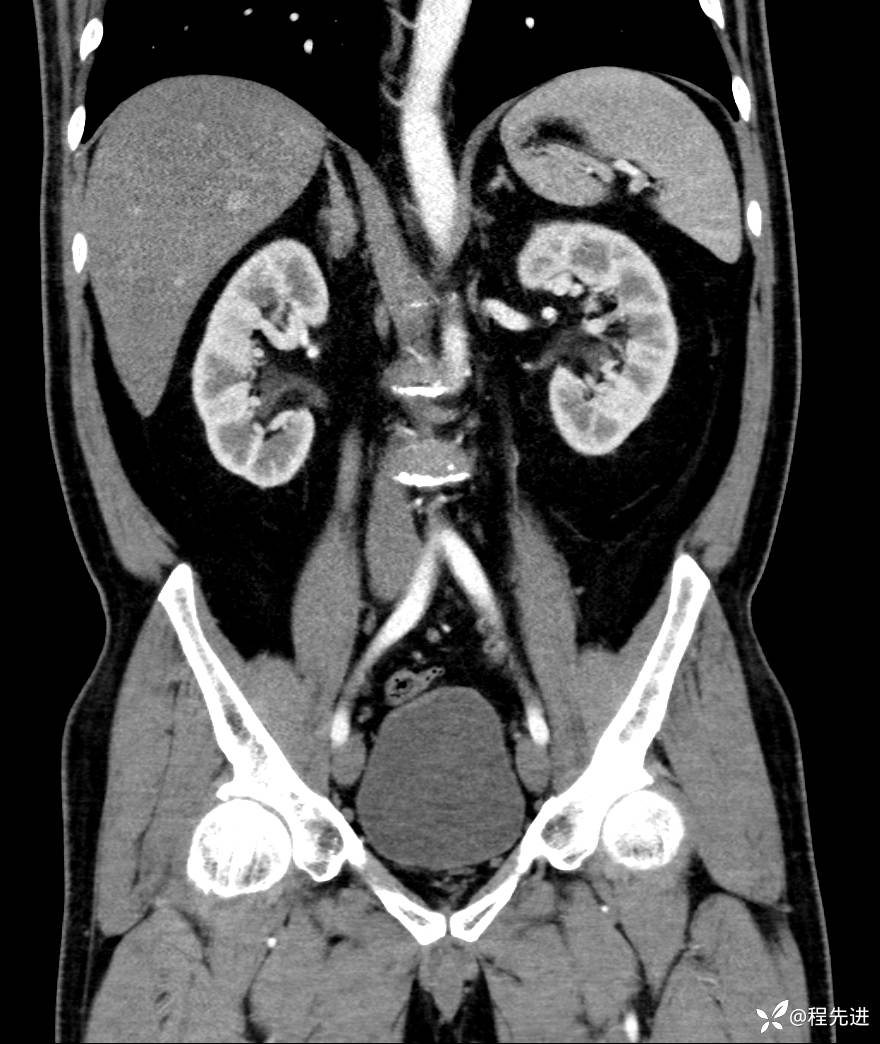

【腹盆】特别精彩病例|发现腹膜后肿物1月余

患者性别:男

患者年龄:42岁

主诉:发现腹膜后肿物1月余

现病史:患者1月余前查体,行超声检查提示:后腹膜囊实性肿块;慢性胆囊炎伴胆囊内结石;无腹痛腹胀,不伴腹泻发热等;偶感腰背部酸痛。

CT平扫+增强: